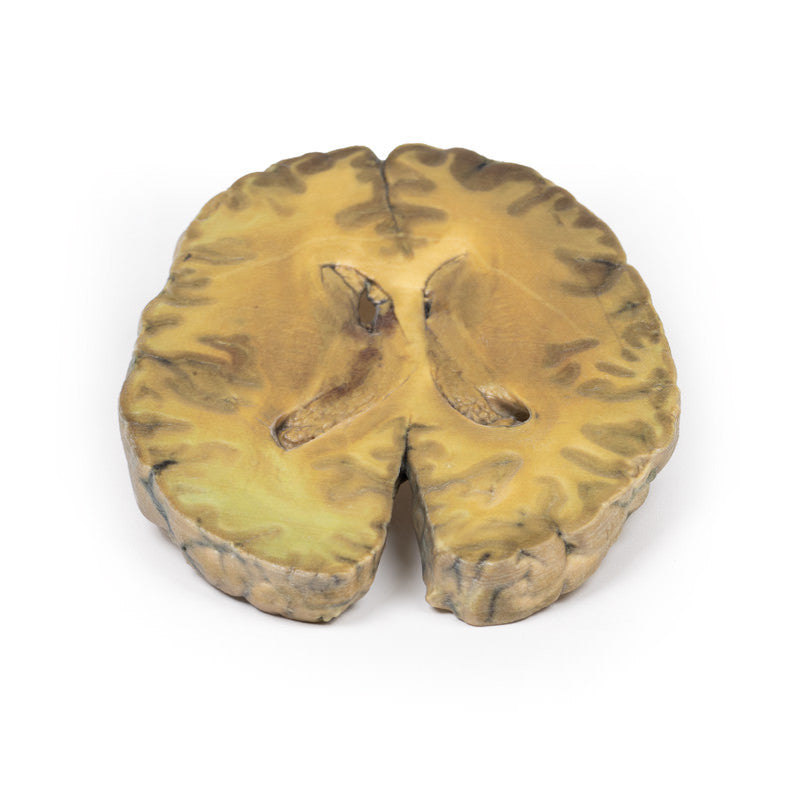

This specimen is an example of ventriculitis, with pneumococcal meningitis and right basal pneumonia also being found at autopsy. The horizontal slice through both cerebral hemispheres displays both of the lateral ventricles. The ventricles show a thickened, rough ependymal lining with cellular debris accumulation around the choroid plexus and also in the anterior horn. The lower surface shows similar changes and also displays the normal arrangement of the caudate nucleus, lentiform nucleus and internal capsule. Histology demonstrated extensive infiltration of neutrophils in the sub-arachnoid space as well as multifocal severe (sub)endothelial infiltration with obstruction of vascular lumen and involvement of the blood vessel walls. The inflammation extended into the cerebral parenchyma causing haemorrhage and necrosis.